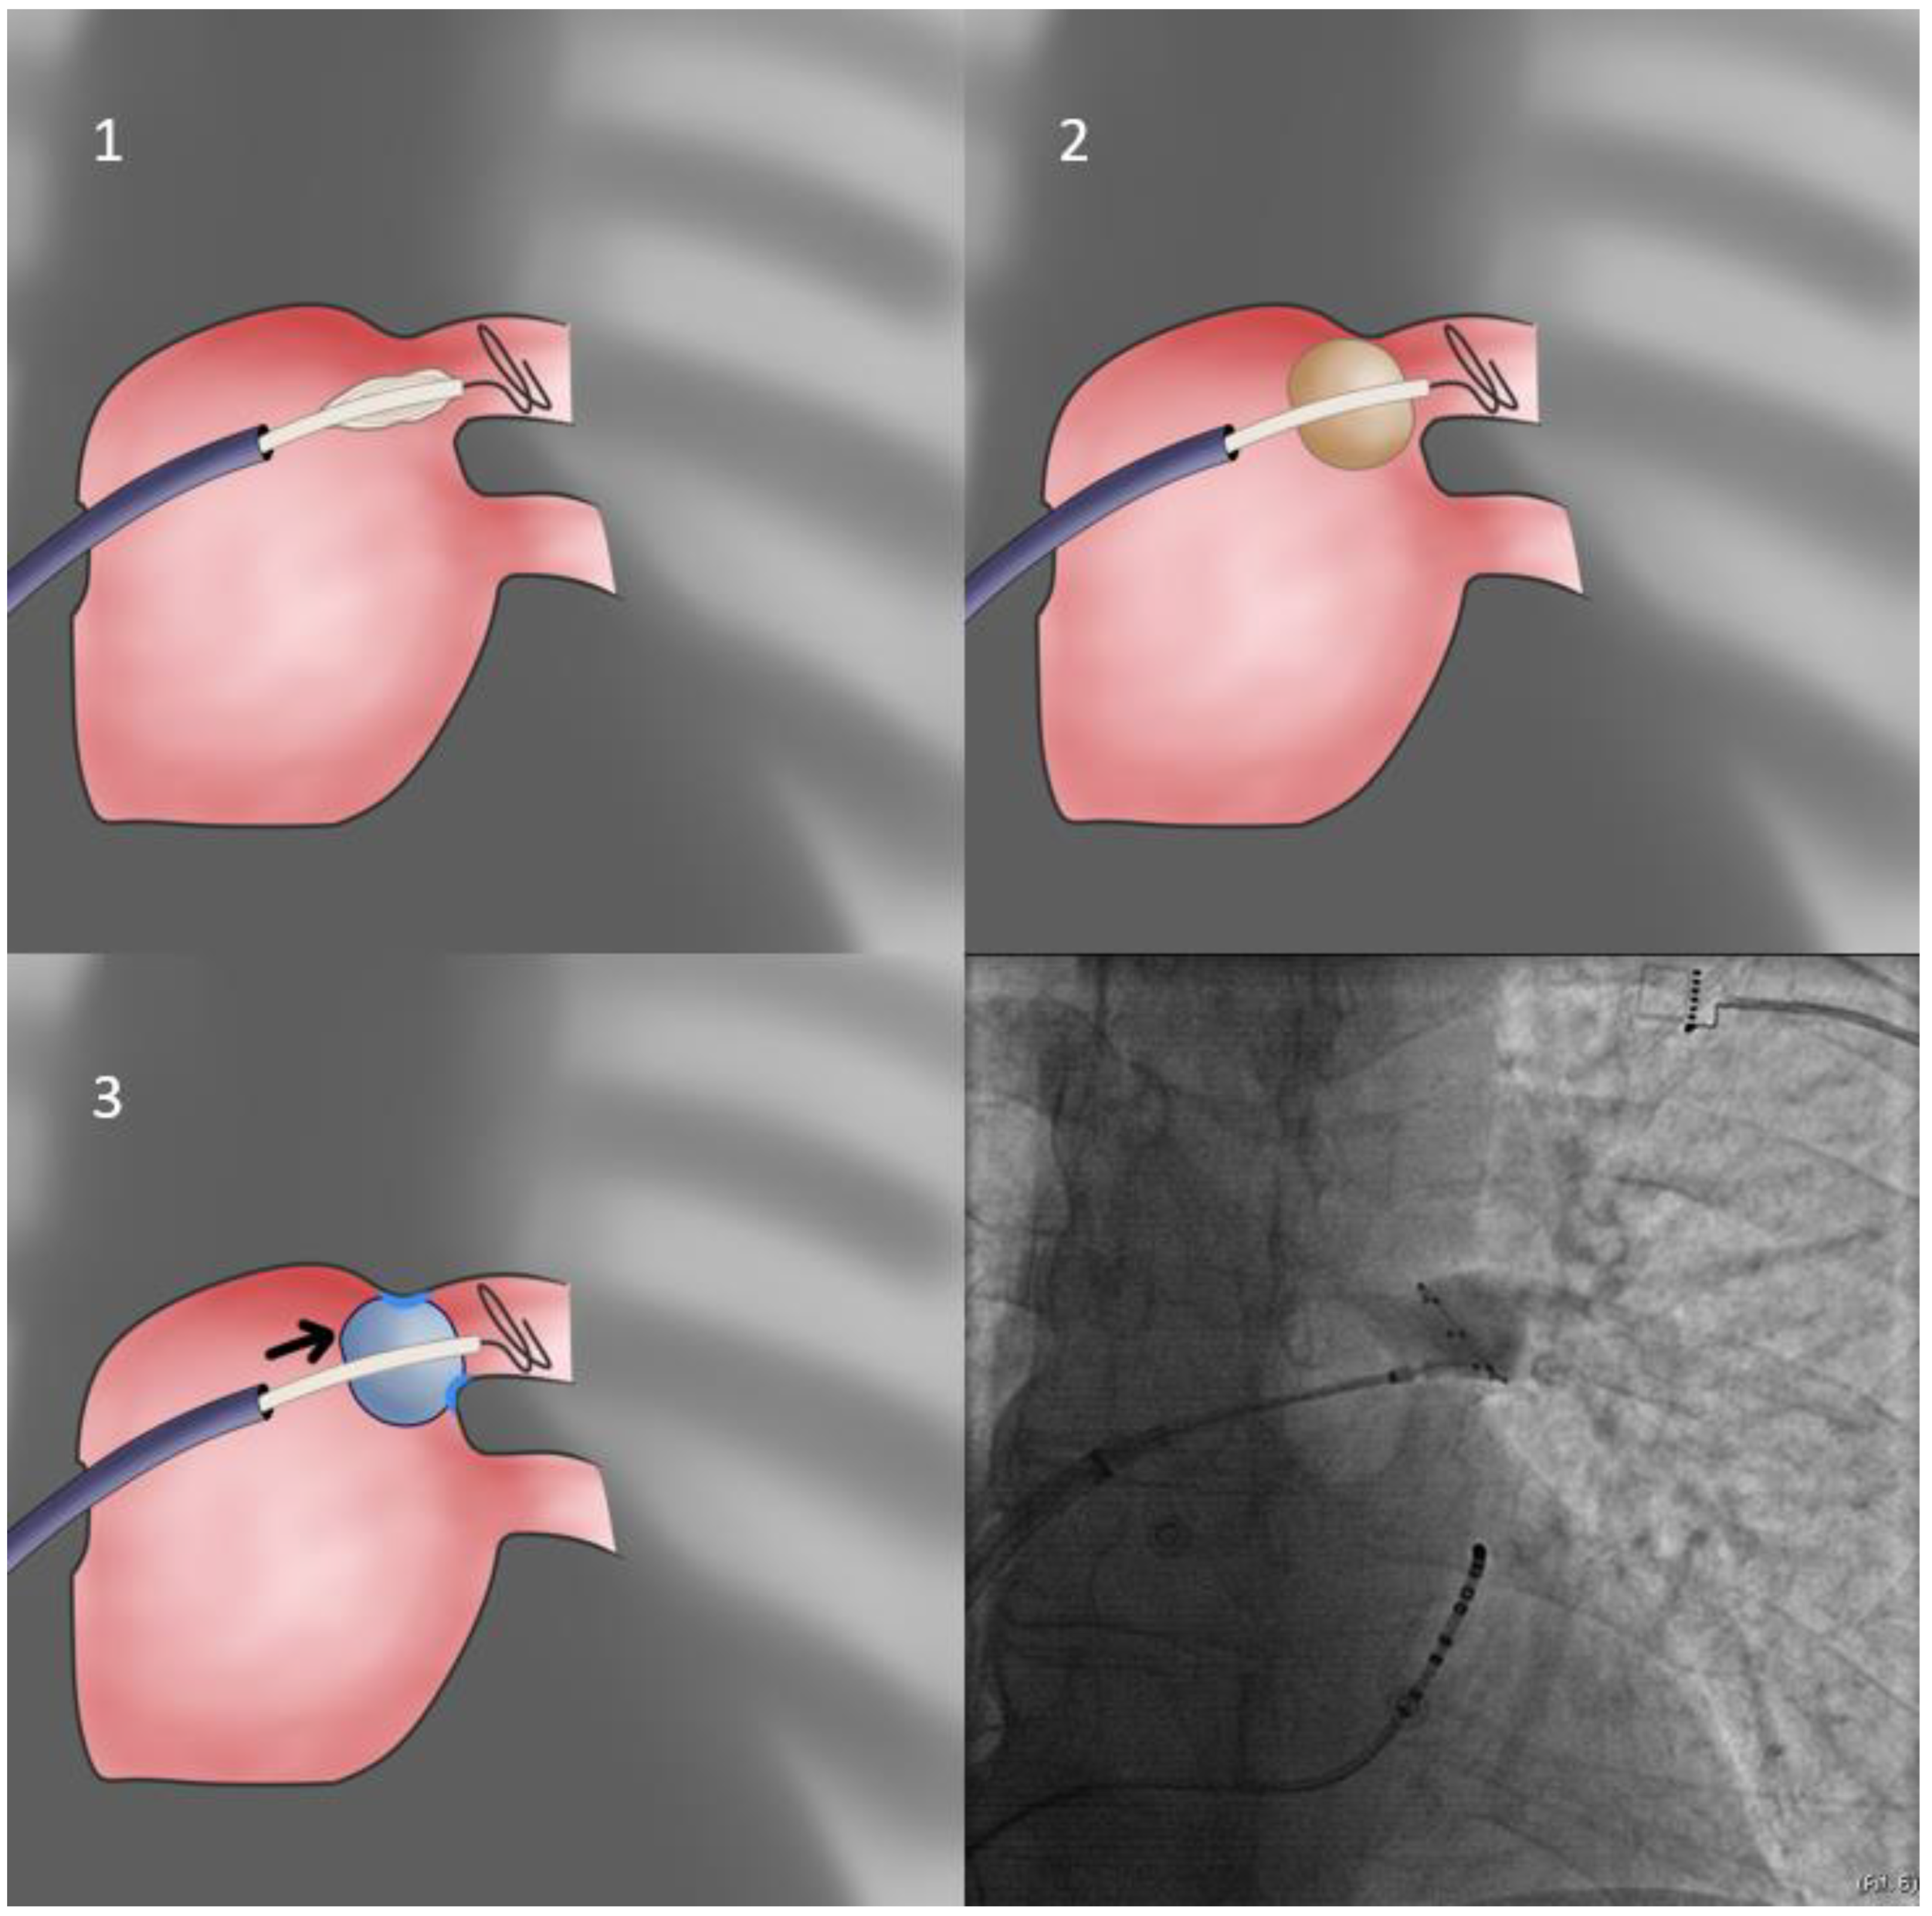

- In cases of extremely sized antra and despite proper orientation, sealing is unattainable; the operator may elect to push the sheath forward only after freezing has begun, since freezing increases CB diameter from 26 to 28 mm, rendering it more likely to properly occlude the antrum (delayed occlusion approach—Figure 4). Usually, the cue for sheath pushing is the initiation of a steep temperature drop on the monitoring console screen, several seconds after freezing has commenced. In even rarer cases, where this approach is ineffective, and conversion to a point-by-point approach is undesirable, one may deliver lesions in a sequential manner, targeting each quadrant of the antrum separately, without occlusion, evaluating the effect after completion of the quartet of applications (segmental approach).